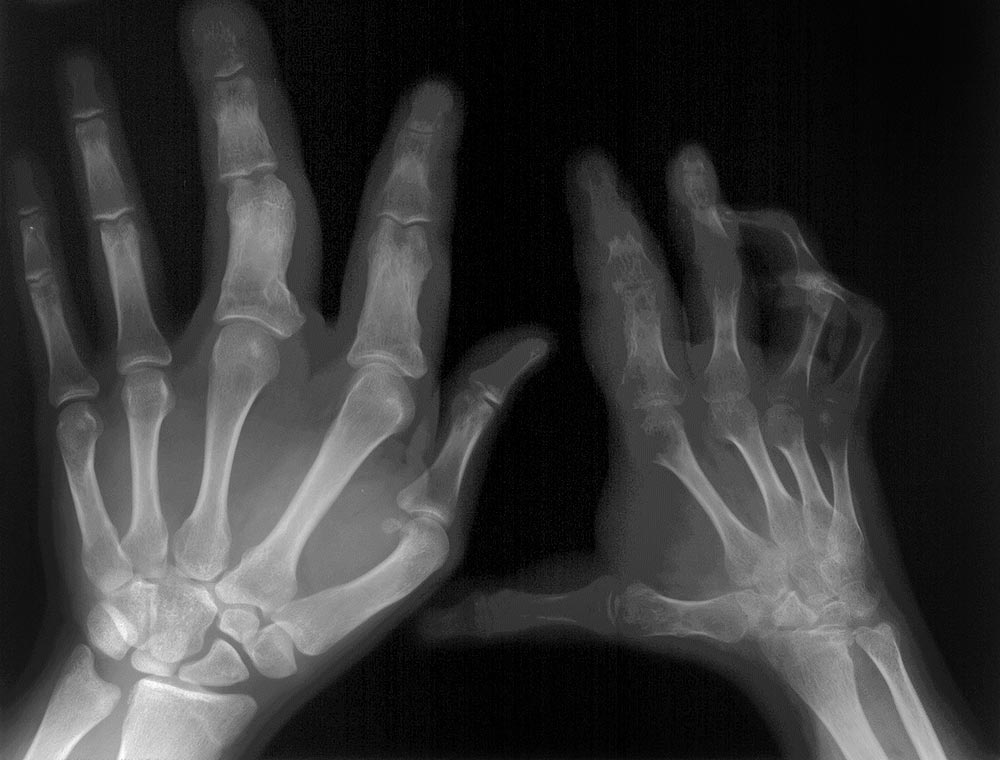

Phänotypen aus dem Spektrum der PIKCA-assoziierten umschriebenen Überwuchssyndrome mit ganz überwiegender Weichteilkomponente in Form eines lipomatösen/fibroadipösen Überwuchses und häufig skelettaler Mitbeteiligung. Die Gefäßveränderungen sind dabei ganz untergeordnet und liegen wenn, dann nur als kapilläre Malformationen (KM) vor. Bei einer Beteiligung großer Gefäße in Form von Gefäßmalformationen erfolgt die Zuordnung des Krankheitsbildes zum CLOVES-Syndrom. Minimalvariante des Fibrolipomatösen Gigantismus ist die Macrodactylia fibrolipomatosa.

Von Geburt an Asymmetrie durch umschriebenen Großwuchs im Bereich der Extremitäten (meist Füße) beim fibrolipomatösen Gigantismus oder einer Körperhälfte beim Hemihyperplasie-multiple Lipomatose-Syndrom (HHML). Subkutane, viszerale, muskelinfiltrierende regionale Lipomatosen, seltener Lipome. Im Verlauf oft Progredienz des fibrolipomatösen Überwuchses. Bei HHML ist das Wachstum eher proportional und nicht überschießend, während beim fibroadipösen Überwuchs das klinische Bild durch einen umschriebenen, progressiveren Gigantismus geprägt ist.